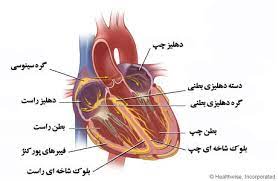

قیمت: 48٬000 تومان - دسته بندی فایل: علوم پزشکیپاورپوینت انانومی فیزیولوژیک عضله قلب

فروش ویژه پاورپوینت حرفه ای انانومی فیزیولوژیک عضله قلب با تخفیف استثنایی فقط 84000هزار تومان تعداد اسلاید : 41 اسلاید